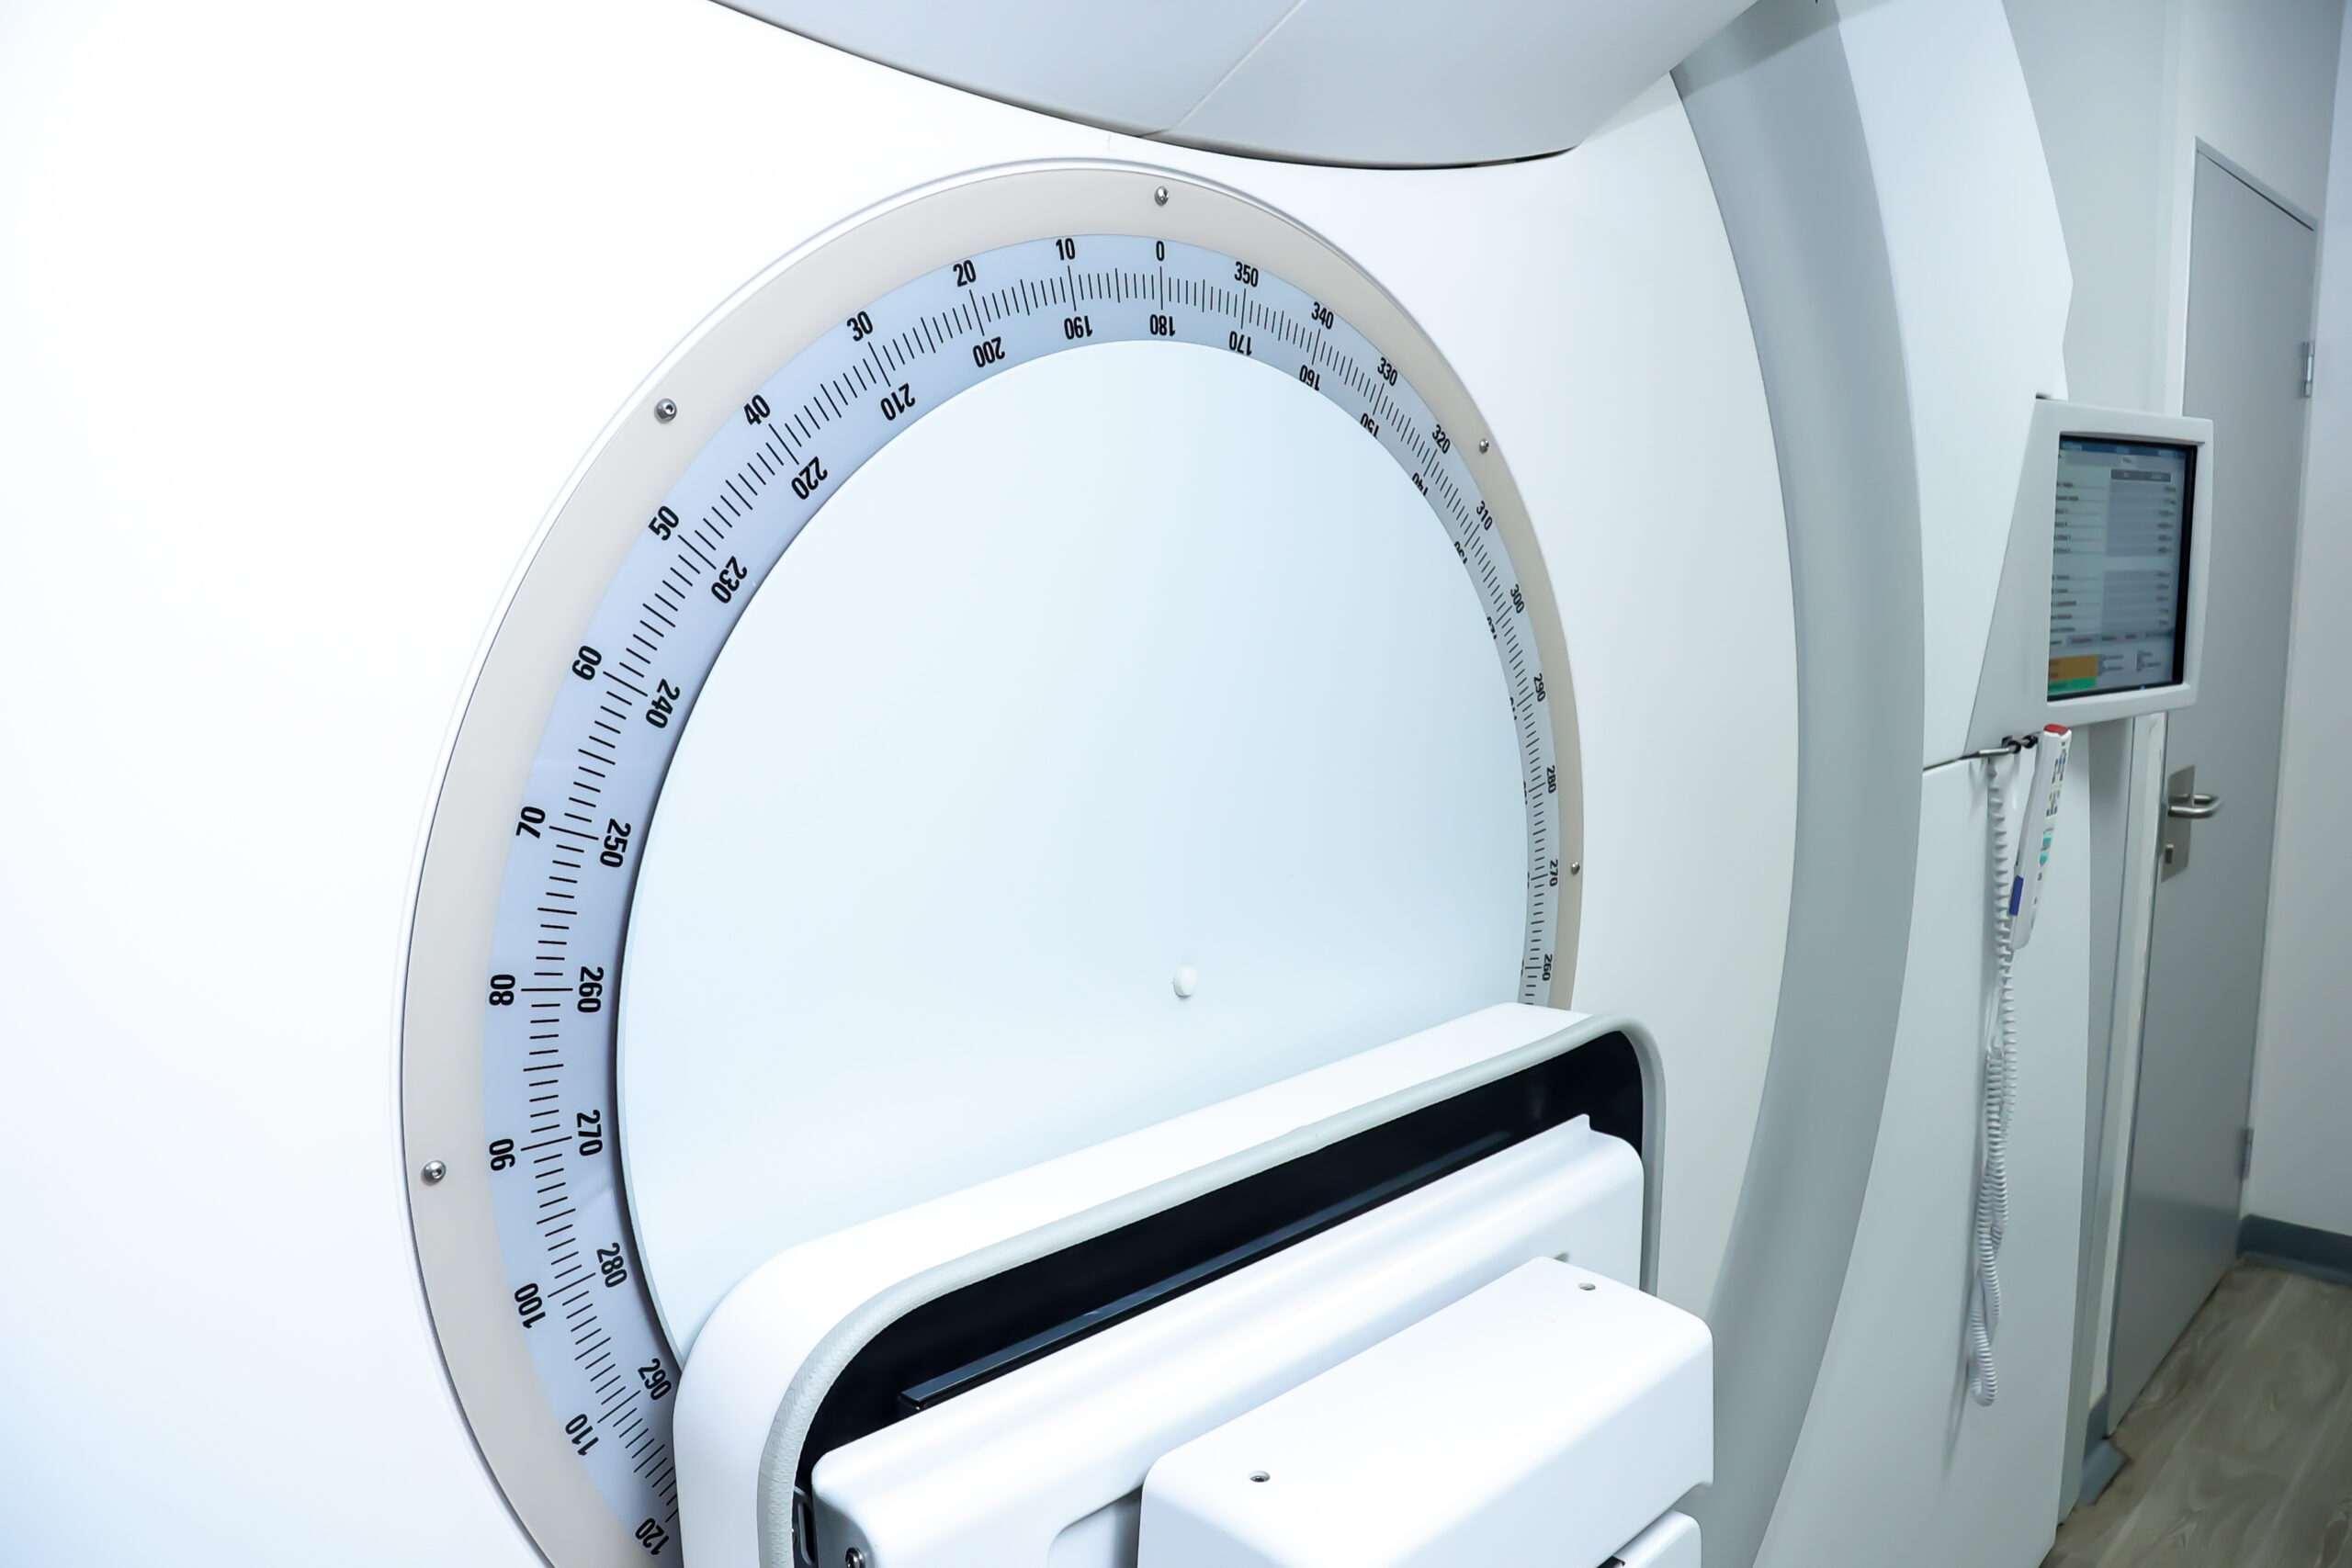

External beam radiation is the most common source type of radiation treatment.

Radiation beams are aimed from a linear accelerator, which penetrate the body to reach the cancer site. -